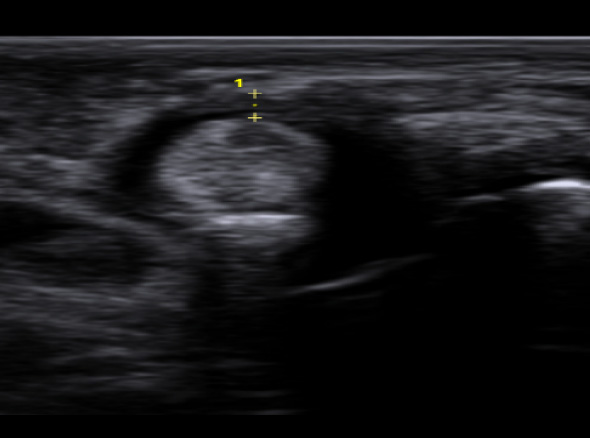

학술적으로는 협착성 굴곡건염이라고 표현하고, A1 활차라는 터널에 굽히는 힘줄이 마찰되다가 힘줄의 내부적인

변화가 일어나 병이 생긴 상태를 의미합니다. 내부적인 변화가 심해질 경우 힘줄이 부어 결절을 이룰 수도 있는데

이러한 경우 A1 활차에 끼어서 딸깍 거리거나 걸려서 안 펴지는 증상이 생깁니다.